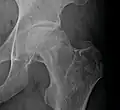

X-ray images of avascular necrosis in the early stages usually appear normal. In later stages it appears relatively more radio-opaque due to the nearby living bone becoming resorbed secondary to reactive hyperemia.[2] The necrotic bone itself does not show increased radiographic opacity, as dead bone cannot undergo bone resorption which is carried out by living osteoclasts.[2] Late radiographic signs also include a radiolucency area following the collapse of subchondral bone (crescent sign) and ringed regions of radiodensity resulting from saponification and calcification of marrow fat following medullary infarcts.

Radiography of avascular necrosis of left femoral head. Man of 45 years with AIDS. -